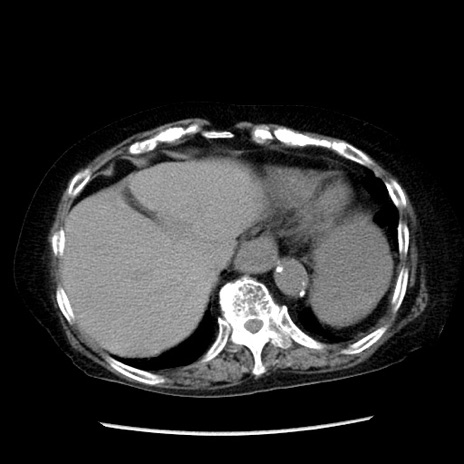

症例14(横断像)

【症例】 90歳代女性

【主訴】 腹痛・嘔吐

【現病歴】今朝から左側腹部痛を認めた。 経過観察していたが、嘔吐を認めたため来院。

【既往歴】 子宮癌術後

【身体所見】 意識清明、BP 127/54mmHg、P 98bpm Sp02 95%(RA)、BT 35.8°C、腹部平坦・軟腸ぜん動音聴取良好、右下腹部圧痛(+) 反跳痛なし

【データ】WBC 9800、CRP 0.46